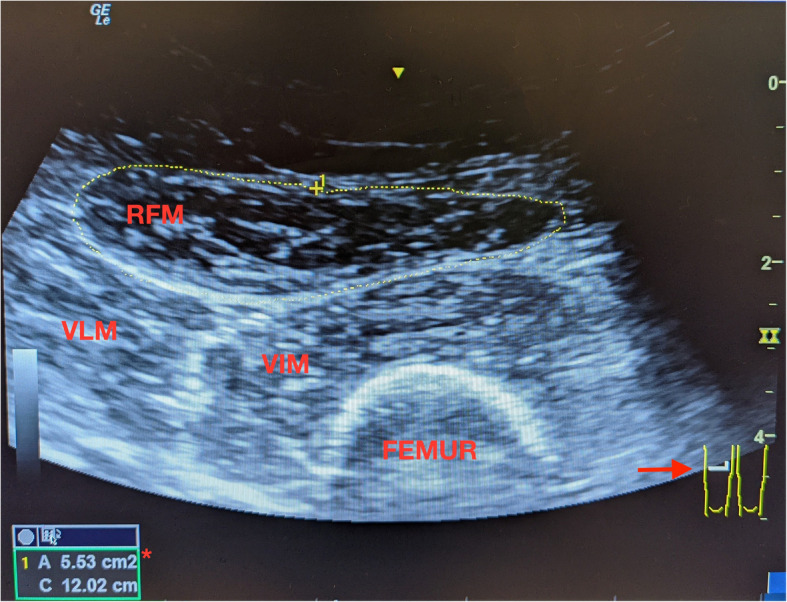

Methods: In a prospective single center cohort study, we investigated the association between muscle mass and short-term outcomes after kidney transplant. Patients undergoing kidney transplant between November 2019 and October 2020 were enrolled. We quantified muscle mass by ultrasound measurement of the rectus femoris cross-sectional area. The primary outcome was the number of days alive and out of hospital within 30 days of surgery. Incidence of surgical complications by the Clavien-Dindo system was also evaluated.